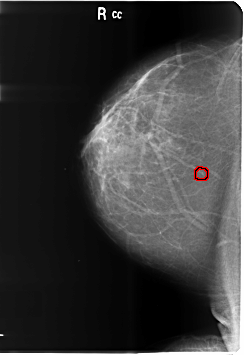

B_3486_1.RIGHT_CC

RIGHT_CC LINES 6024 PIXELS_PER_LINE 4144 BITS_PER_PIXEL 12 RESOLUTION 50 OVERLAY

FILE: B_3486_1.RIGHT_CC.OVERLAY

TOTAL_ABNORMALITIES 1

ABNORMALITY 1

LESION_TYPE CALCIFICATION TYPE PLEOMORPHIC DISTRIBUTION CLUSTERED

ASSESSMENT 4

SUBTLETY 3

PATHOLOGY BENIGN

TOTAL_OUTLINES 1

BOUNDARY